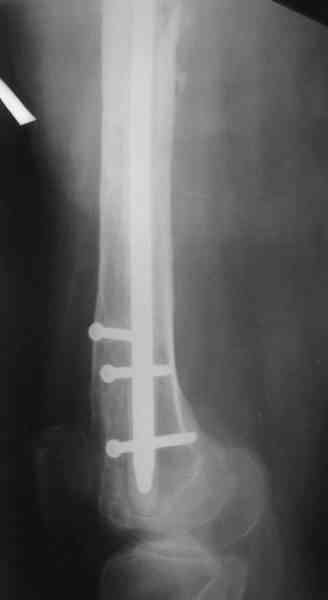

1, 2, 3, 4 - рентгенограммы бедра от 8 августа этого года (через четыре месяца после операции);

В настоящее время наш пациент ( см. http://weborto.net/forum/1177351385/) ходит с одним костылем. У него периодически открывается свищ на задне-наружной поверхности бедра с умеренным серозно-гнойным отделяемым. Температура тела и анализы нормальные. На рентгенограммах имеются признаки консолидации ложного сустава.